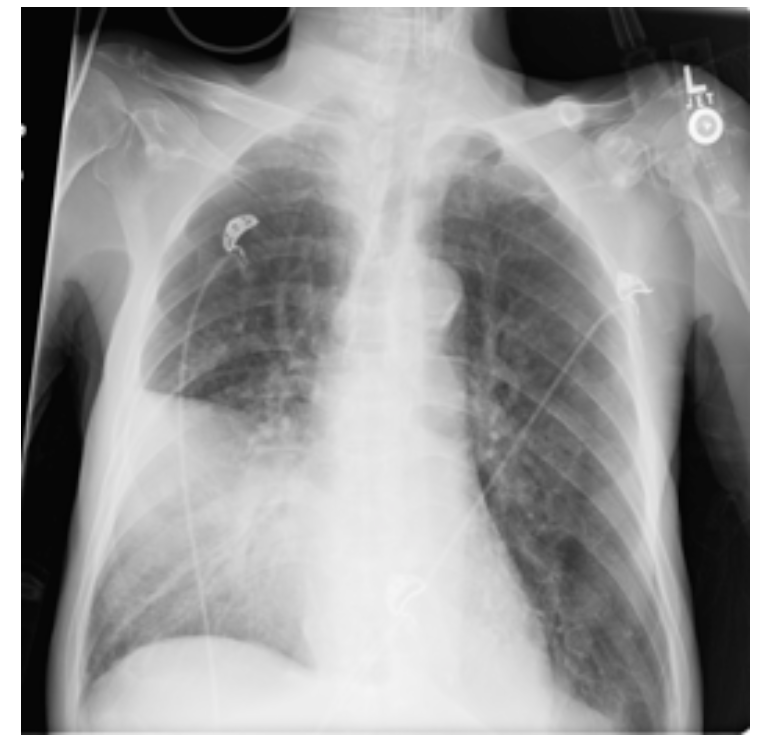

Q

Where is the problem?

A

• Consolidation in the right middle lobe.

• Lobar pneumonia.